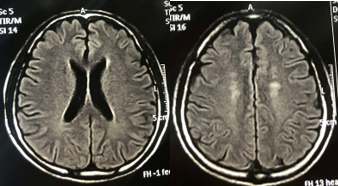

Chụp Cộng hưởng từ sọ não (4/4/2019):

Hình 1:  Hình ảnh chụp MRI sọ não: Nhiều nốt ngấm thuốc mạnh rải rác ở nhu mô não trên và dưới lều, theo dõi tổn thương thứ phát (mũi tên đỏ).